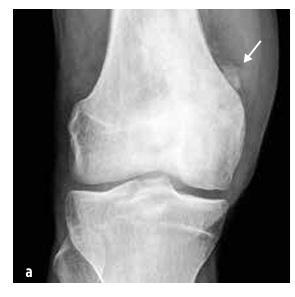

Септичний артрит зустрічається в 50 % випадків у дітей віком до двох років, а в 75 % випадків уражаються суглоби нижніх кінцівок (коліно > стегно > гомілка) (див. малюнок № 4). Остеомієліт найчастіше локалізується в метафізі.

Про інфекцію кістки або суглоба слід думати у дитини з раптовим розвитком: лихоманкою, незрозумілим кульганням та/або аномальним положенням кінцівки, відмовою використовувати кінцівку, обмеженням обсягу рухів, м’язово-скелетним болем ± місцевим болем при пальпації суглоба або кістки та набряком з почервонінням (див. малюнок № 4). CAVE маленькі діти локалізують біль неточно (наприклад, біль переноситься з стегна в область коліна).

Зображення № 4

Клінічні дані при септичному артриті